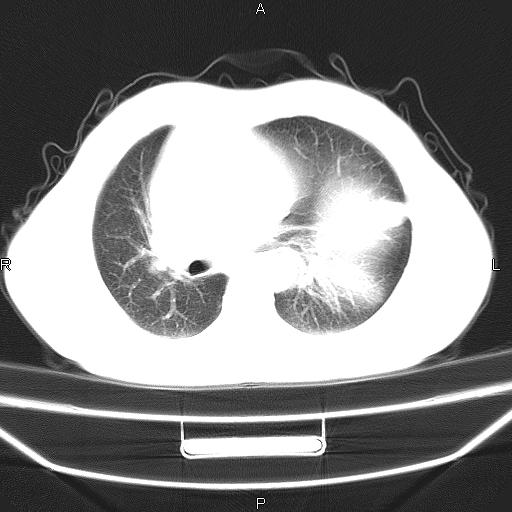

患者,男。50岁。近几日有咳嗽症状,无其他不适,既往病史无,考虑膈疝。请前辈们看看指导指导。

膈膨升,左下肺通气不良,膈肌好像还完整。

考虑左侧膈疝。

左侧膈疝。

符合隔膨升,膈肌较完整。